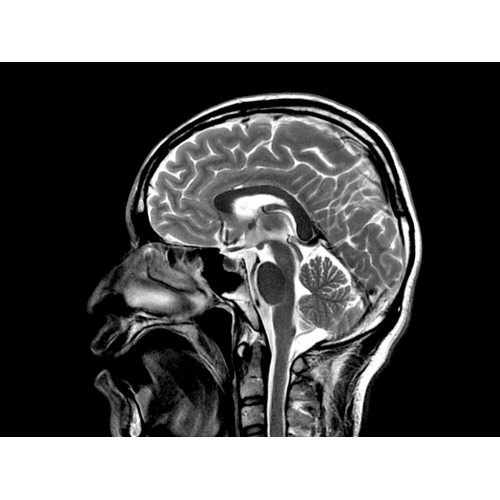

МР-томограф с широким туннелем Optima MR450w является настоящей рабочей лошадкой и может эффективно обслуживать большее число пациентов. Томограф обеспечивает одновременно удобство пациента, продуктивность работы, отличное качество изображения. В этой МРТ-системе инженерам компании удалось без компромиссов совместить необходимый объем перемещения с удивительно высоким качеством изображения.

Благодаря принципиально новым технологиям мы расширили возможности МР-томографов с широкими туннелями, совместив непревзойденное качество изображений с высокой производительностью при широком — 50 см — поле зрения.

МР-томограф Optima MR450w позволяет получать изображения исключительно высокого качества, которые помогают установить диагноз. Чтобы удовлетворить ожидания клиентов в отношении высокого качества, в МР-томографе Optima MR450w были сохранены дополнительные возможности платформы Discoverу, привнесшие в его работу универсальность и мощь.

• Магнит переработанной конструкции — полностью новый магнит длиной 145 см обеспечивает однородную контрастность тканей в удобных для пациента условиях.

• Цифровой РЧ-приемник OpTix — эксклюзивная оптическая РЧ-система увеличивает четкость сигнала и его интенсивность, формируя чистые и резкие изображения.